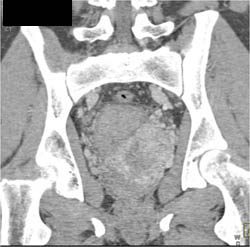

Diagnosis

Arrhythmias Causing Motion on Aortic Valve